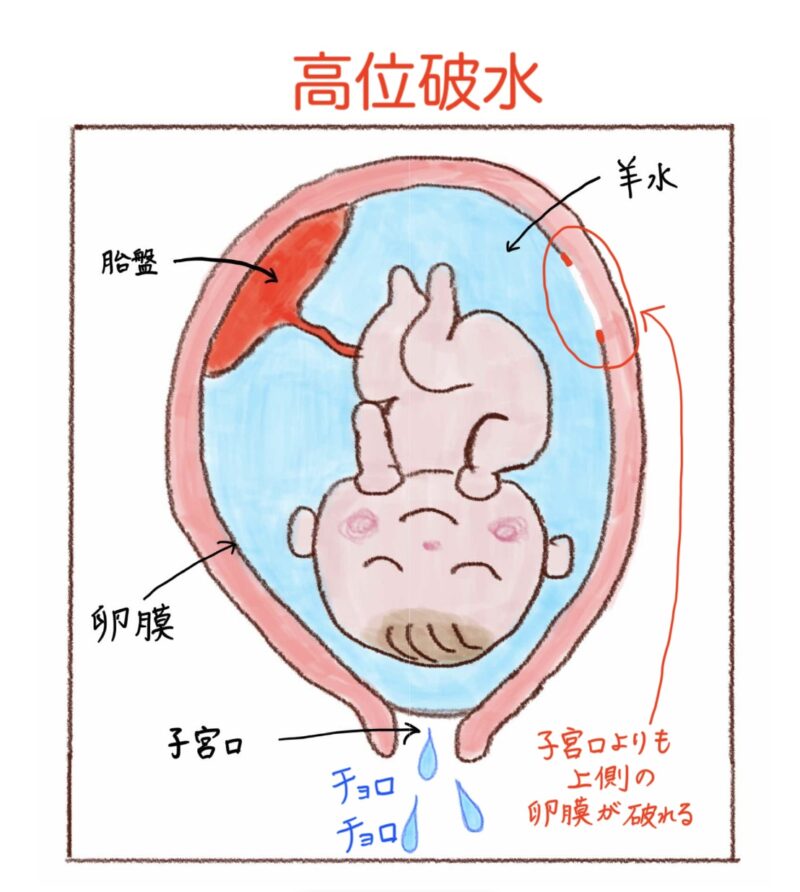

破水

破水とは、赤ちゃんを包んでいる膜(卵膜)が破れて羊水が出てくることです。

ちなみに、破水には2種類あって、

二つ目は、「高位破水」といって、赤ちゃんの身体側の卵膜の一部が破れることです。

この場合は、おりものが出たのか、尿もれなのかよくわかりにくいことが多く、下着が湿っている事で気づく人もいます。

破水かどうか迷ったとしても、自己判断で様子をみずにすぐに連絡をしましょう。